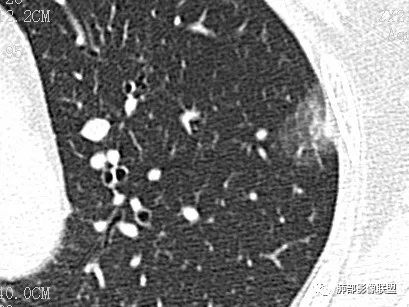

case2 医学百科网 | YxBaike.Com

男 48 2019-05-04

Clover: 医学百科网 | YxBaike.Com

鳞癌

请说一下诊断依据 这例有咳嗽发热 医学百科网 | YxBaike.Com

Coke with ice:

泥沙样钙化,坏死明显,支气管阻塞,阻塞肺炎

小鱼: 医学百科网 | YxBaike.Com

分叶,血管凹陷进入,内坏死,壁厚薄不均,坏死边界不清,肺门淋巴结大,鳞癌 医学百科网 | YxBaike.Com

光明:

右肺下叶肿块,湖泊样坏死,壁厚薄不均匀,肺门淋巴节肿大,考虑鳞癌 医学百科网 | YxBaike.Com

错过:

厚璧空洞伴不均一致坏死,支气管堵塞伴阻塞性肺炎,考虑鳞癌

崇军:

分叶,无毛刺,坏死明显,壁厚薄不均,阻塞性肺炎,复查壁变得更薄,支持鳞癌 医学百科网 | YxBaike.Com

小鱼:远端阻塞肺炎,脐凹

毛勤香: 医学百科网 | YxBaike.Com

厚壁空洞分叶状,近端支气管壁增厚,湖泊样坏死,治疗23天后坏死增多,周围炎症有吸收,增强其内血管显示欠清,考虑鳞癌 医学百科网 | YxBaike.Com

泥沙样钙化的疾病谱有什么?鳞癌,神经内分泌?记不起来了 医学百科网 | YxBaike.Com

@曹冠杰 细沙样钙化在神经内分泌癌多见,鳞癌偶尔可以有

坏死位于远侧,近侧比较实

@姚鹏 腺癌坏死少见,阻塞性炎症也少,胸膜播散多见,癌性淋巴管炎多见,有所不同。 医学百科网 | YxBaike.Com

6个月后增大,坏死更明显了 医学百科网 | YxBaike.Com

病理诊断 医学百科网 | YxBaike.Com

鳞癌 医学百科网 | YxBaike.Com

一句话小结:

右肺下叶背段不规则块影,浅分叶,密度不均,轻度强化,壁厚不均,坏死及空洞明显。病灶边界可分辨,相关支气管狭窄截断。肺门见肿大淋巴结。

符合典型肺鳞癌影像学表现。

半年后任由块影坐大匪夷所思。